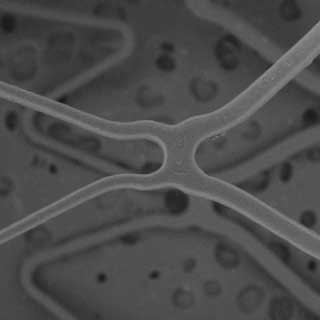

WiZeCell™

Stent Design

Adaptive cell size designed for optimal scaffolding and uniform drug dosing while preventing tissue prolapse.

Low cobalt-chromium footprint with ultra-narrow 40µm and 72µm struts.

EluNIR PERL’s optimized cell size ensures uniform scaffolding and prevents tissue prolapse and strut overlap.